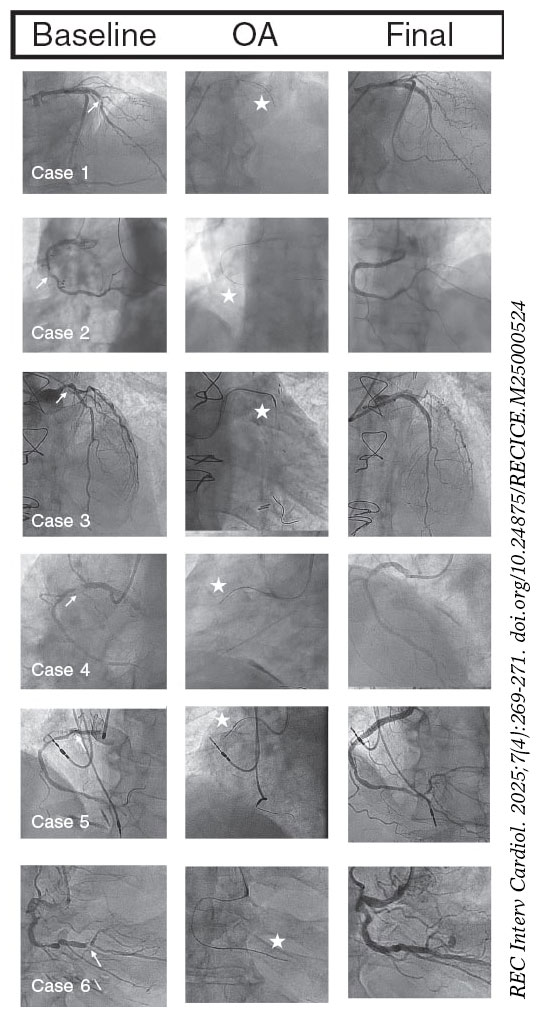

In all our cases, OA was successful, with the crown crossing the lesion and allowing subsequent angioplasty without major complications. Figure 1 illustrates the angiographic images of each case.

Figure 1. Baseline coronary angiography, orbital atherectomy (OA), and final coronary angiography. The arrows point to the uncrossable lesion, and the stars indicate the OA crown.